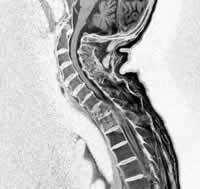

在各种食管畸型中食管闭锁最常见,约占85%。本病若不行治疗数日内即可死于肺部炎症和严重失水。近年来由于新生儿麻醉方法的改进,新生儿监护的开展,静脉高营养的应用,外科技术的进步,食管闭锁的治愈率有明显的提高。但若发现较晚已并发严重的肺内感染者,则疗效不佳。故加深对本病的认识,早期发现、早期诊断、早期治疗是提高疗效的关键。发病率约为每3000个活婴中发生1例,故并非罕见。发病男女无差别。